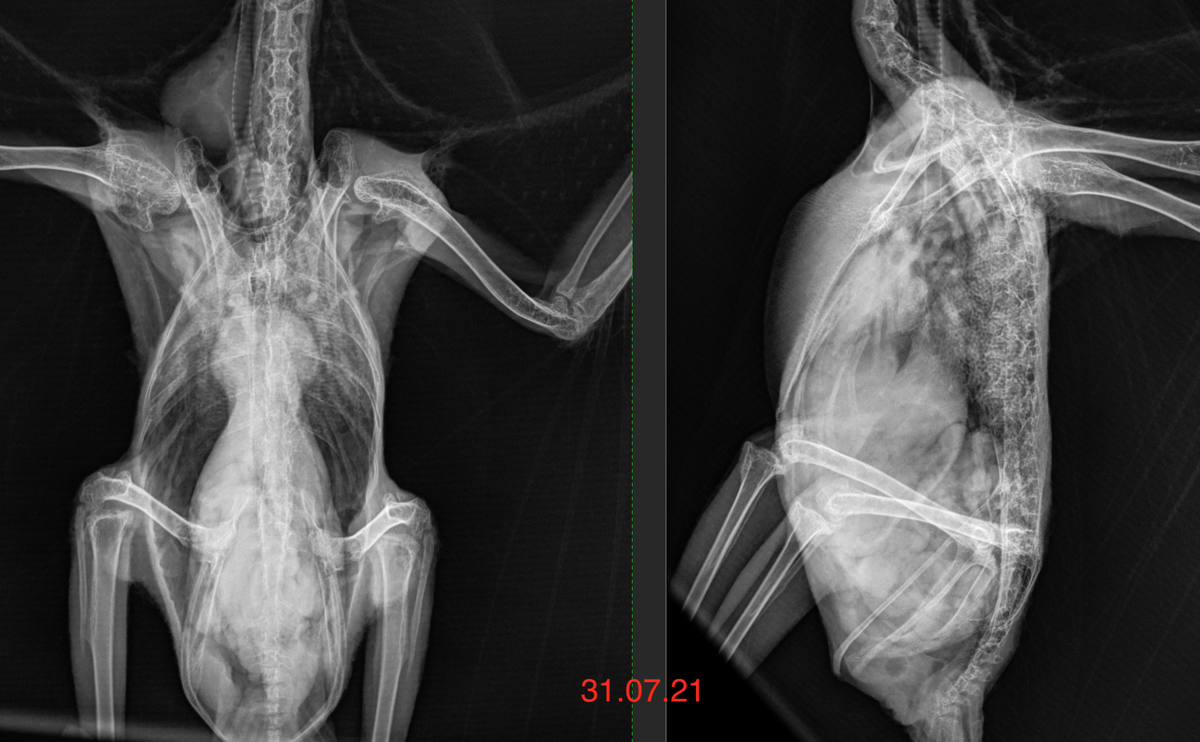

То есть это рахитичная птица, почти сразу же у нее был обнаружен микобактериз вызванный M.genavense, далее было очень много анализов, лечение от кучи всякой вторичной микрофлоры, в том числе заражение от человека MRSA, и т.д., но борнавироз не удавалось подтвердить, лечение от борнавироза было назначего по изменениям увиденным на рентгене, и через 4 года лечения результат можно увидеть на втором рентгене.

Железистый желудок почти нормальных размеров.

Ответ: "Возможно, даже на стадии клинического обострения, когда желудок огромный. Пример результата лечения вы видите на рентгене."